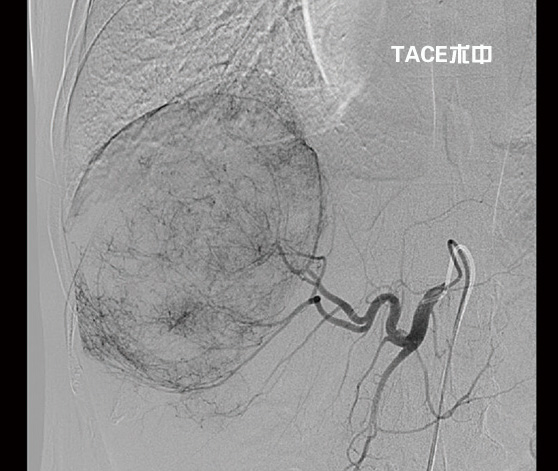

劉大爺在濰坊市市立醫(yī)院普外科接受了2次介入治療——經(jīng)皮經(jīng)股動(dòng)脈穿刺肝動(dòng)脈選擇性造影并肝癌灌注化療栓塞術(shù)(TACE)后,不僅巨大肝癌明顯縮小,而且又成功實(shí)施了肝第Ⅶ段、第Ⅵ段切除手術(shù)。日前康復(fù)出院時(shí),劉大爺精神抖擻,滿面笑容,還調(diào)侃說(shuō)癌癥再厲害也敵不過(guò)濰坊市市立醫(yī)院普外科專家的手術(shù)刀。

“這種情況不宜切除右半肝,因?yàn)樽蟀敫误w積小,余肝不能代償,切除后會(huì)導(dǎo)致肝功能衰竭,危及生命。必須先行介入治療,把供應(yīng)肝臟腫瘤的血管堵死‘餓死’癌細(xì)胞,使癌瘤縮小,左肝代償增大,待肝癌降期后再行手術(shù)治療,效果會(huì)比較好,也比較安全。”普外科首席專家李森主任分析說(shuō)。

期間劉大爺共經(jīng)過(guò)了2次介入治療,一個(gè)月前他來(lái)普外科復(fù)查時(shí)醫(yī)生告訴他腫瘤已明顯縮小,可以手術(shù),劉大爺心里一陣高興。